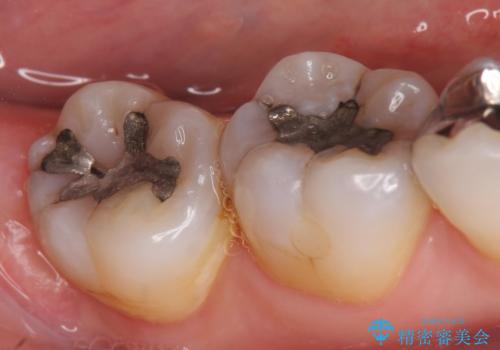

- 右下奥歯の古い銀歯をやり直したいといらっしゃった方の症例です。

銀歯を除去後、セラミックインレーにて修復しました。